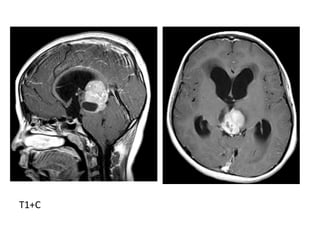

CT+C shows homogenous enhancement of the mass which assumes a

triangular shape as it conforms to the contours of the pulvinar of

the thalami and velum interpositum

T1

T1+C

b) Pineoblastoma :

-Highly malignant PNET (Primitive Neuroectodermal

Tumors)

-In patients with trilateral retinoblastoma, Pineoblastoma

may develop in patients with familial and or bilateral

retinoblastoma

-(Exploded calcifications) along outside of mass

(peripherally), unlike germinoma which engulfs and

induces calcification of the pineal gland

-Dense enhancement

-Larger, more heterogeneous with much greater

propensity for local invasion and CNS dissemination